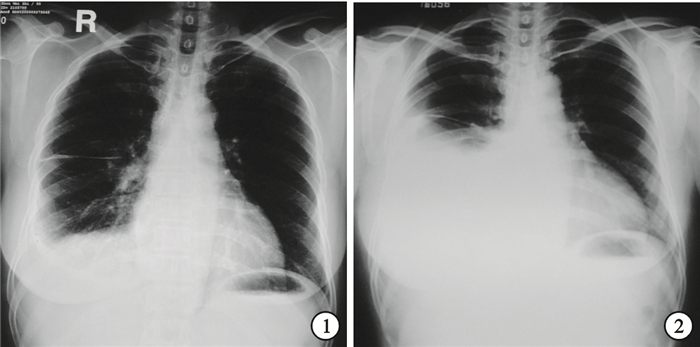

臨床資料 患者女性,50歲。因“間斷干咳、胸痛2個月,加重伴氣短1個月”于2005年9月26日入院。患者2個月前無誘因間斷出現咳嗽及右側胸痛,深吸氣時明顯,無發熱、咳痰、咯血及呼吸困難。胸部X線片示右側少量胸腔積液(圖 1),在外院行胸腔穿刺胸腔積液檢查為單核細胞為主的滲出液,考慮為結核性胸膜炎,予異煙肼、利福平和乙胺丁醇三聯抗結核治療1個月,胸痛繼續加重,并出現活動后胸悶氣短,復查胸部X線片示右側胸腔積液明顯增多(圖 2)。為進一步診治入我院。自發病以來,患者食欲下降,二便正常,近2個月內體重減少8 kg。既往史:高血壓2年,無煙酒嗜好,無毒物接觸史。入院后體格檢查:體溫36.9 ℃,脈搏 108次/min,呼吸18次/min,血壓135/85 mm Hg(1 mm Hg=0.133 kPa)。淺表淋巴結未觸及腫大;頸軟無抵抗,氣管居中,甲狀腺不大,右下背部叩診為濁音,聽診呼吸音減弱,未及胸膜摩擦音,腹平軟無壓痛,肝脾肋下未及,雙下肢不腫。入院診斷:胸腔積液原因待查。